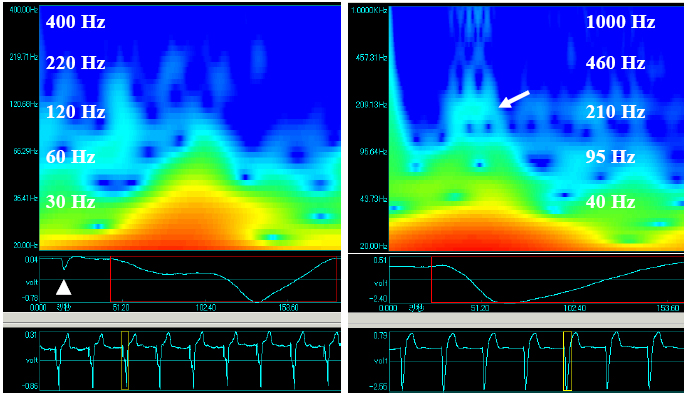

Figure 4. The contour of wavelet transformed signals was obtained from the right ventricular pacing beat in the left panel and they were obtained from the left bundle branch block with the anterior myocardial infarction in the right panel.

In general, it is difficult to diagnose MI in the case with IVCA. The time-frequency analysis may help to solve this problem since it can detect the independent abnormal excitation sequence due to the focal necrosis of MI. We tried to examine this point in the cases of MI with and without IVCA. The examples were illustrated in Fig. 4. The left panel in Fig. 4 shows the wavelet transformed signal from the patient treated with the implantation of permanent pacemaker in which the cardiac excitation is generated by right ventricular pacing. The patient did not complicate by MI, according to other clinical examinations. The white triangle indicates the pacing pulse. The higher frequency power can be hardly seen between QRS in this case. The right panel shows the wavelet transformed signal from the patient of the left bundle branch block (LBBB) with the anterior MI simultaneously. The higher frequency power is clearly observed in the early phase of the QRS indicated by the arrow.